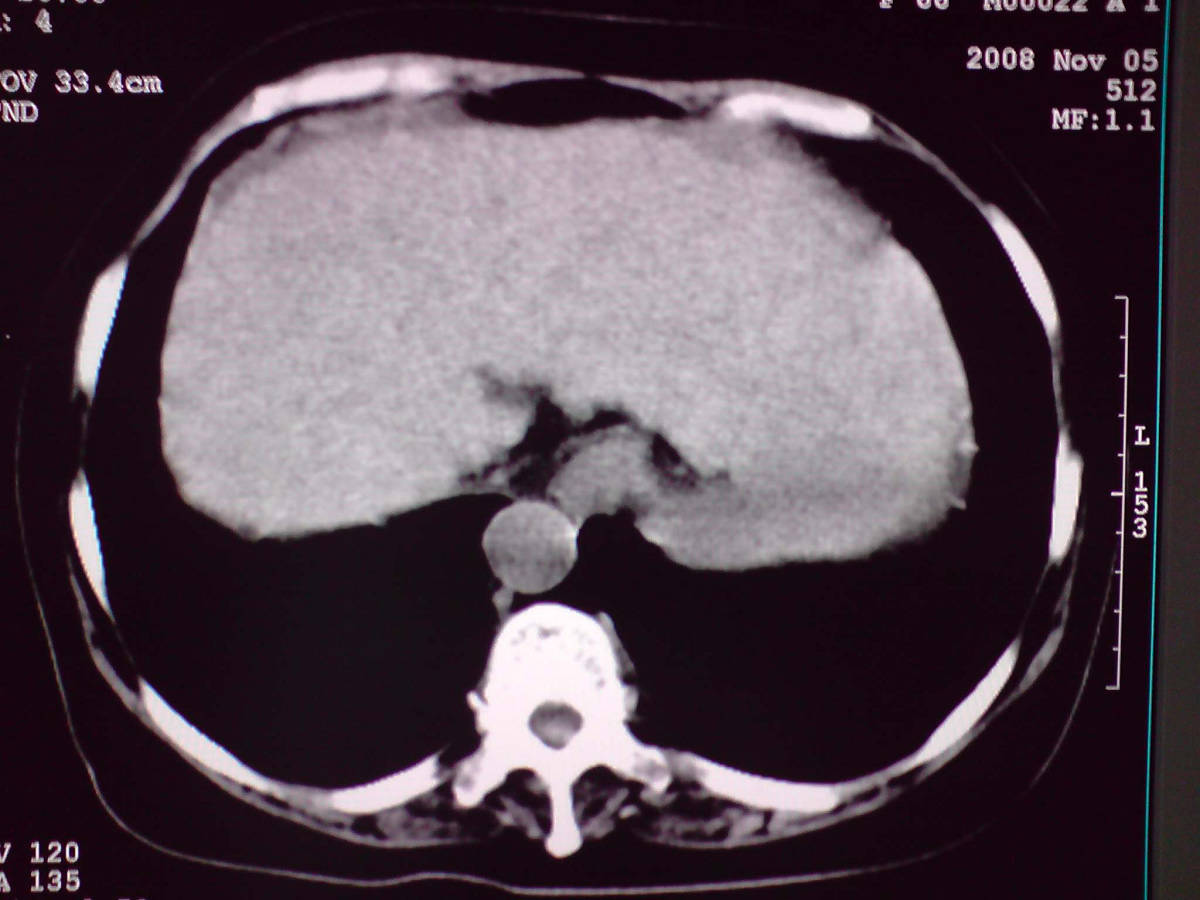

女性,60岁,上腹不适、自感胃部疼痛

小网膜区见类圆形软组织密度肿块,密度不均,内见不规则低密度区,与肝左叶分界模糊,肝脏体积缩小,密度不均匀,边缘呈波浪状,尾状叶明显增大,脾脏下缘明显超出肝脏下缘。

意见:肝硬化并外生性肝癌,建议增强扫描。

肝脏比例失调,形态失常,外缘呈波浪状,腹腔内肿块内见低密度区并与肝脏界限欠清

考虑外生性肝癌,左肺下叶占位,肝硬化

有肝硬化背景,肝胃间隙见不规则形,且密度不均匀的占位性病变,与肝左叶分界不清,首先考虑外生性肝癌可能性大,不排外肝胃间隙恶性占位肝脏受侵可能性。左肺下叶结节影,其内见空泡征,边缘见毛刺,从一元化的角度首先考虑转移。

1 肝脏各叶比例失调,形态失常,外缘呈波浪状。右叶萎缩,左叶 尾叶增大。2 腹腔内软组织密度肿块,低于肝实质密度,内见低密度区,并与肝脏界限欠清。腹膜后见肿大淋巴结,并与腹腔肿块关系密切。3 左肺下叶肿块,见边缘毛刺征及胸膜凹陷征,并与近肺门侧见异常血管相连。

肝脏比例失调,形态失常,外缘呈波浪状,腹腔内

小网膜区肿块内见低密度区并与肝脏界限欠清

考虑恶性间质瘤,左肺下叶占位,肝硬化

1肝胃韧带区域一肿块,肿块上缘与肝左叶相连。肝硬化。考虑肝外生型肝癌可能性大,不除外间质瘤。2左肺下叶背段一结节,有偏心性空洞,长毛刺,其周有多发小结节。考虑结核可能性大。

感谢大家的讨论,今天拿到病理结果是肝细胞癌